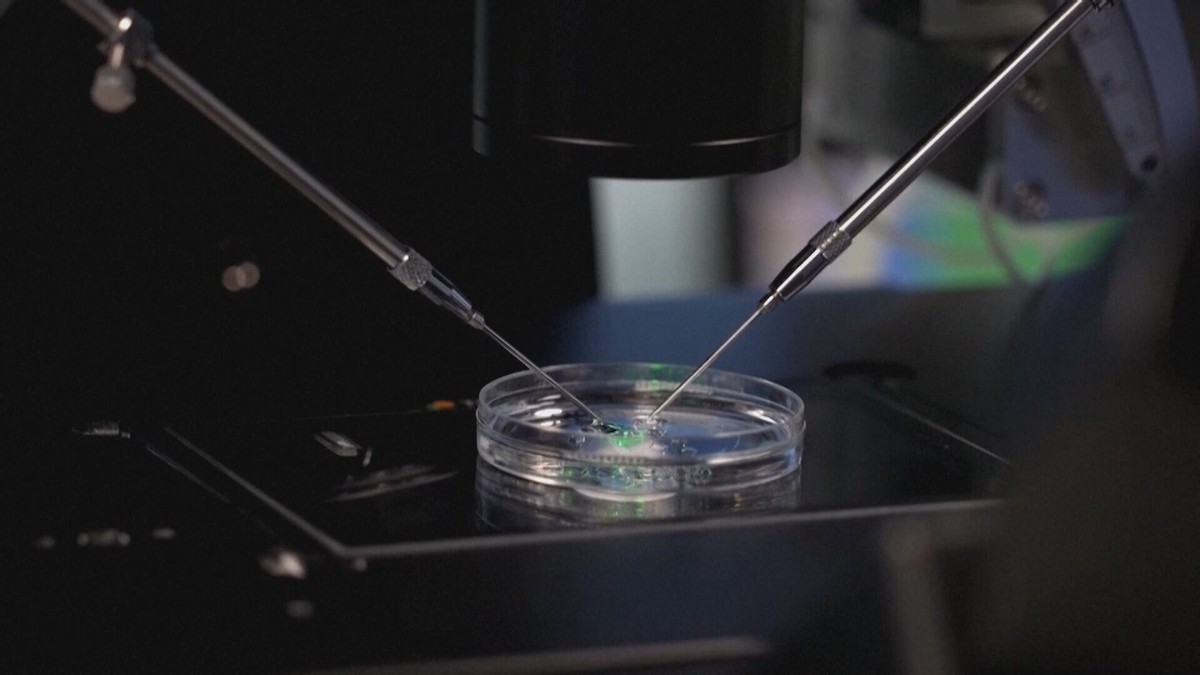

Výzkum ukázal, že konzumace ultrazpracovaných potravin může negativně ovlivnit plodnost, přičemž u mužů se prokazatelně zvyšuje riziko snížené plodnosti a delší doby k dosažení těhotenství, zatímco u žen byly zaznamenány malé odchylky ve vývoji embrya, což podtrhuje význam stravy pro zdraví matek i dětí. #ultrazpracovanépotraviny #zdraví #plodnost

#ReprodukčníChirurgie #Plodnost #Gynekologie